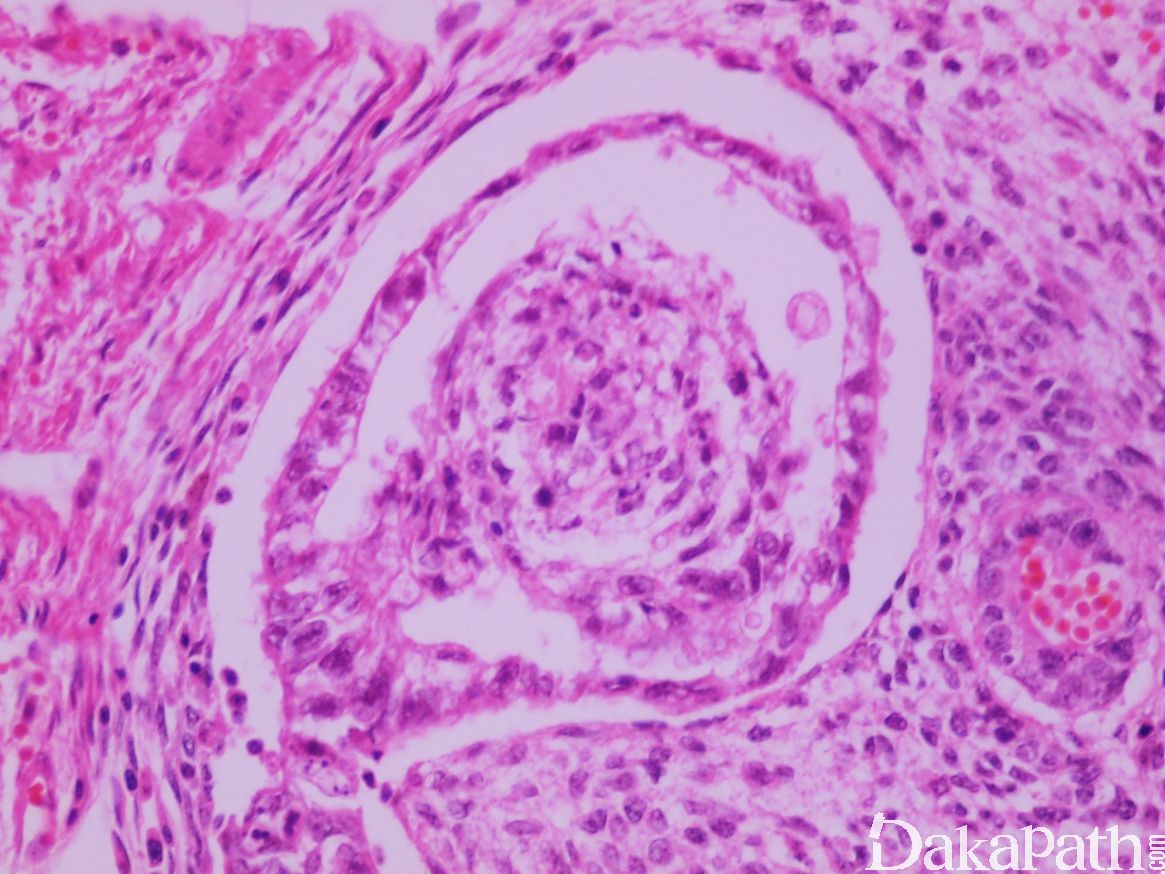

- 显微镜下可见大量散在胚胎样小体,该小体中央为盘状胚胎癌细胞(1-4 层厚),“背侧”可见被覆扁平上皮的羊膜腔(偶尔可被覆为肠型或鳞状上皮),“腹侧”为卵黄囊样囊腔,内含网状或黏液瘤样卵黄囊瘤成分;

- 胚胎样小体约 0.2-0.7cm,均匀分布,周围包绕黏液性胚胎型间叶成分;